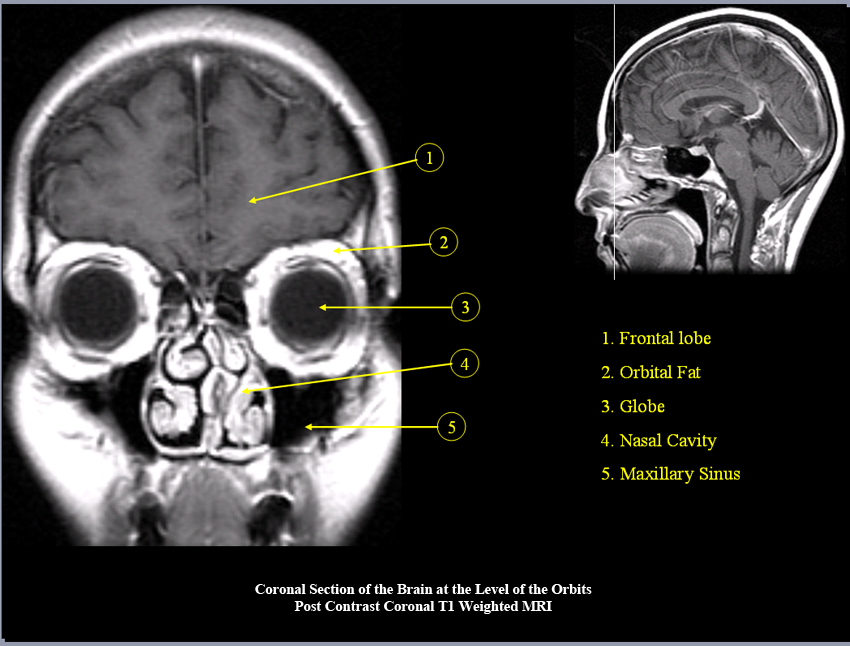

MR Brain and Spine